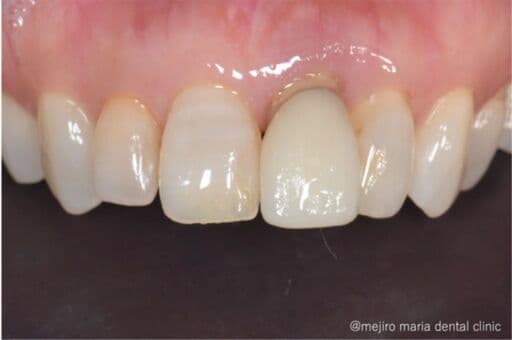

抜歯後の歯茎の凹みを低侵襲で予防し、接着性ブリッジを用いてインプラントを回避_歯槽堤保存術

左上の前歯が歯根破折により保存は難しいと判断された患者様です。抜歯後の補綴治療として、歯をたくさん削るブリッジにも、インプラントにも不安があるということでした。そこで極力侵襲を加えない接着ブリッジという治療法を選択し、なるべく美しい仕上がりになるように抜歯時に歯槽堤保存術を行う事にしました。